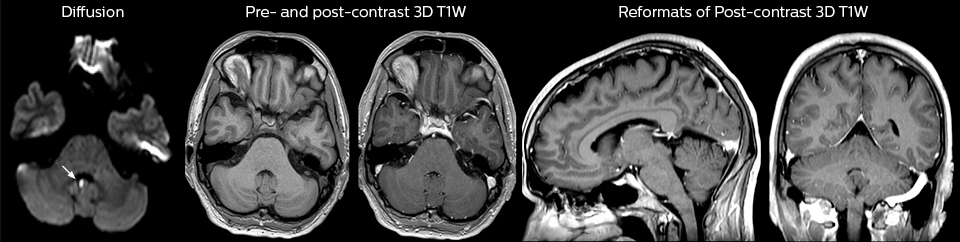

To minimize the time taken to perform scans, rapid MRI examination protocols (ExamCards) were developed, shortening the total scanning time to even less than 10 minutes in some exams. Techniques like mDIXON (modified DIXON) are used for robust capturing of fat-free MRI images in a hectic ED environment.

“We use mDIXON TSE extensively in our spine imaging in the emergency room,” says Dr. Karis. “It’s particularly nice in that it is very robust with regard to susceptibility type of problems that would come up with traditional spectral fat-saturated images; these problems are essentially eliminated with the mDIXON technique. In our ED environment it’s really nice to have the fat-free imaging that goes along with the mDIXON technique.

“For the thoracic and cervical spine routine non-contrast exam, for example, we perform one mDIXON T2 TSE sequence, which provides us with two outputs: the fat-and-water-together T2-weighted images, as well as the water-only sagittal T2-weighted images. And then we also perform an axial gradient echo exam.”

A range of protocol sheets was developed to help ensure that referring physicians order the most appropriate MRI exam. The optimized MRI protocols also include 3D contrast-enhanced imaging, allowing neurosurgeons to comfortably use the isotropic data in the operating room while performing stereotaxic surgery.